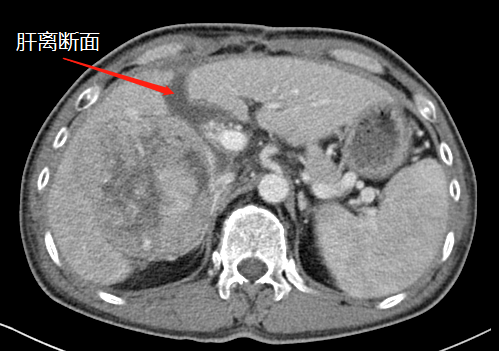

術前CT

近段時間,他因右上腹疼痛就診于瀘州市中醫(yī)醫(yī)院,在檢查中發(fā)現右側肝臟有一12公分左右的包塊,初步考慮為惡性腫瘤,后收治入院。通過全面檢查,診斷其為肝癌晚期,并伴有乙型肝炎、肝硬化等病癥。

“該患者入院后,通過肝臟CT,我們發(fā)現,由于其右肝腫瘤巨大,而正常的左肝體積比較小,手術預切除肝體積達70%以上,術后殘肝體積僅28.3%,再加上該患者存在乙肝和肝硬化,剩余肝臟不足以維持他身體正常運轉所需,不具備肝臟手術切除的基本要求?!焙鷤ケ硎尽?/span>

術前,左肝體積很小